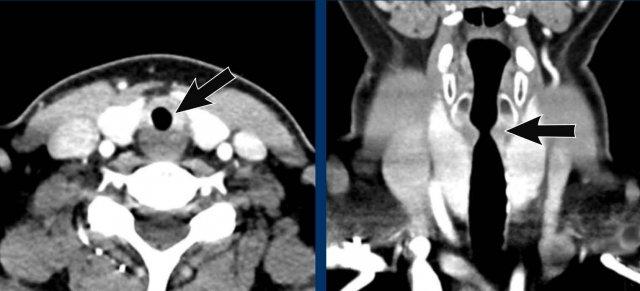

Hạch bạch huyết

Chèn ép phế quản chính phải do hạch bạch huyết to.

Cung động mạch chủ đôi

Bệnh nhân này có cung động mạch chủ đôi gây chèn ép khí quản.